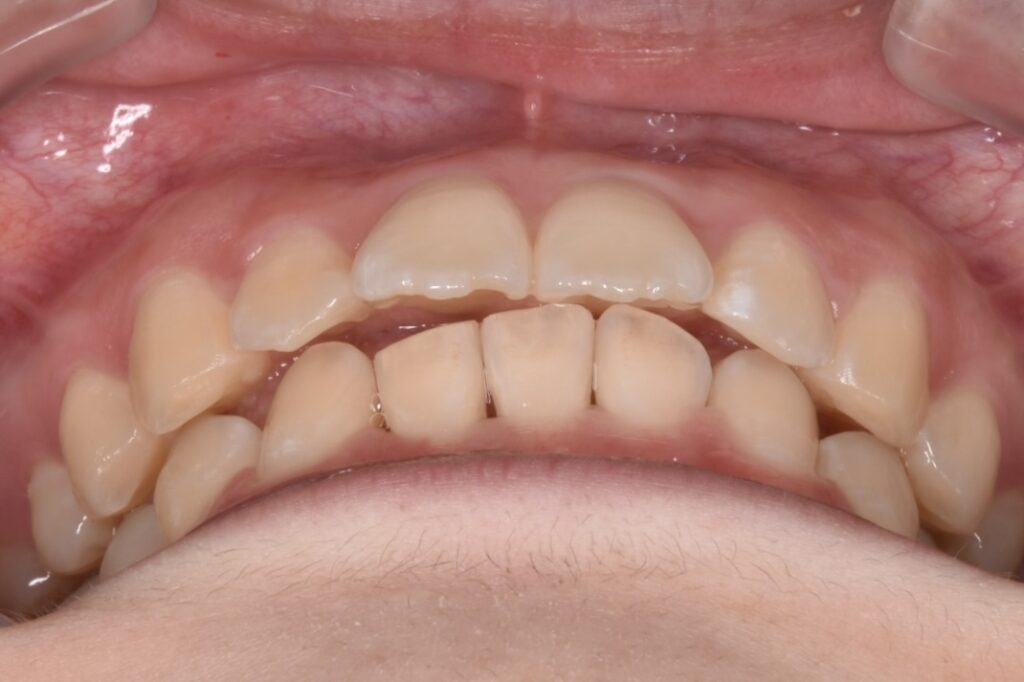

治療後